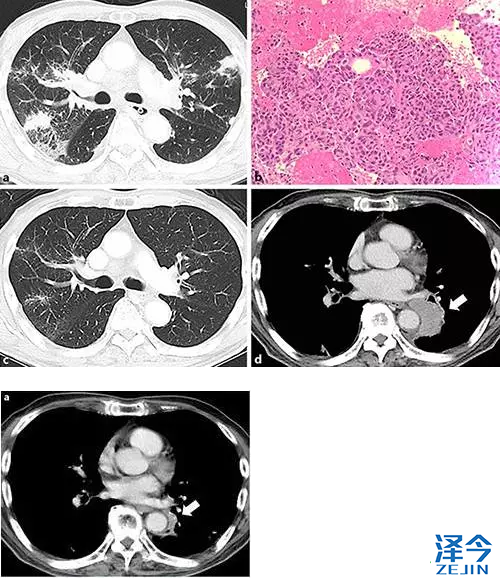

一名有59年吸烟史的76岁男子,因嘶哑,吞咽困难及体重减轻就诊。 耳鼻喉科检查发现左声带瘫痪。 使用增强(CT)进行检查,其显示双侧肺门区域,纵隔和颈部的肺和淋巴结病中的多个结节。 经进一步检查,他被诊断患有肺腺癌(cT1aN3M1a,IV期)(图1a,b)。 基因检测显示ALK融合基因阳性。

nivolumab治疗后肺癌CT检查及胃癌内镜检查。 a在给予nivolumab 5周后,肺部病变显示明显改善(箭头)。